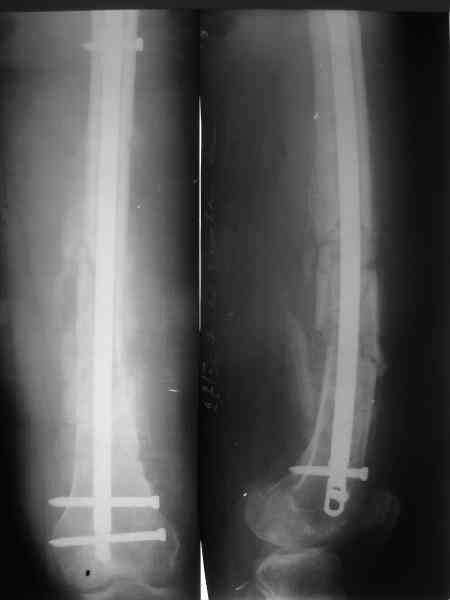

В мае 2007 года оперирована в Уральском НИИТО г. Екатеринбурга. Выполнено: полузакрытое удаление пластины и винтов, IM блокируемый остеосинтез.

На сегодняшний момент (2 месяца после операции). Больная передвигается при помощи трости из-за чувства неуверенности и ощущения онемения в подколенной ямке. В квартире передвигается без дополнительной опоры. Снимки в аттаче.

1. Удалять ли статический винт? Сроки? Способ?

2. Причины и возможные методы лечения индуративного отека н/3 бедра?